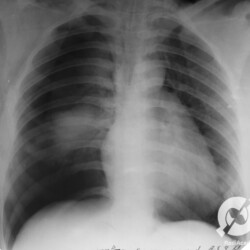

Paciente realizou simpatectomia. Pneumotórax de grande volume à direita. Dá pra ver a linha da pleura e a ausência de parênquima lateralmente a ela. À esquerda, no ápice, também não observamos marcas de parênquima, este também é um sinal de pneumotórax, mesmo que não dê pra enxergar a linha da pleura.